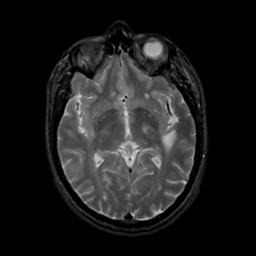

MR Study #16, June 23, 1991 -- Slice #24